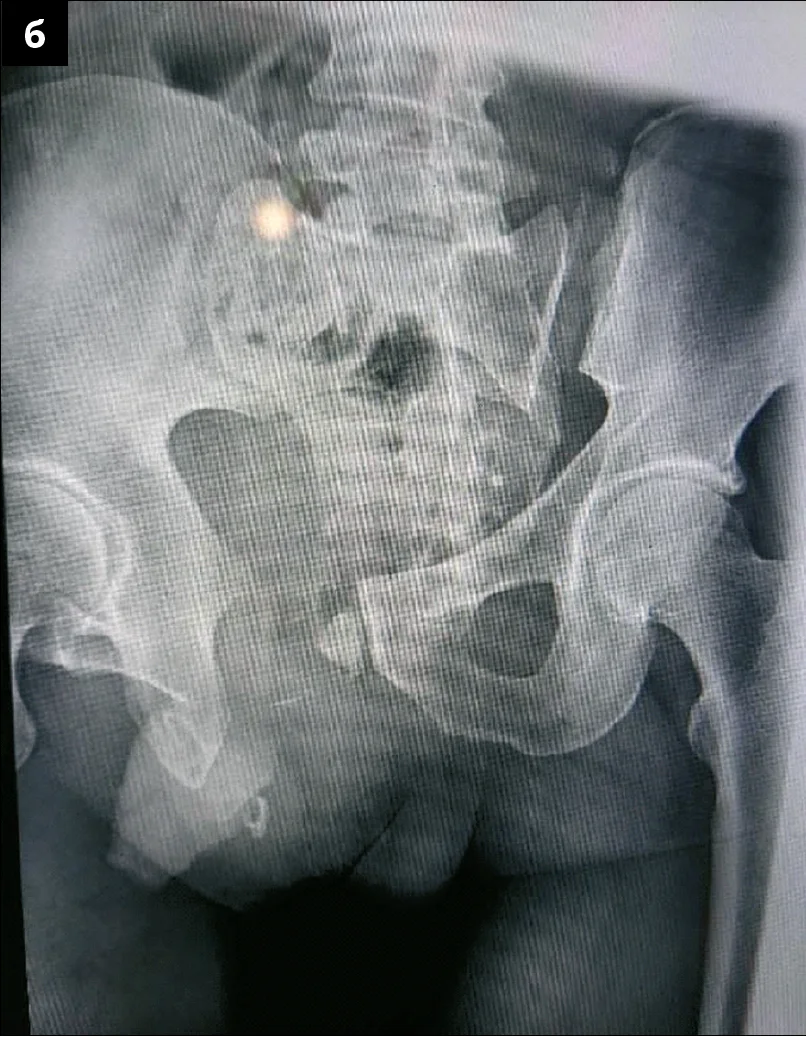

– Продемонструвати можливості та переваги надання спеціалізованої ортопедо-травматологічної допомоги та остаточної хірургічної стабілізації при бойовій механічній травмі таза в наближеному до фронту військово-медичному лікувальному закладі можна на прикладі клінічного випадку закритої бойової травми таза у військовослужбовця 47 років. Пацієнт отримав травму під час боєзіткнення лежачи на животі на землі внаслідок наїзду з лівого боку на ділянку таза гусеничної броньованої машини. Поранений був евакуйований до передової хірургічної групи, де йому було виконано ультразвукове дослідження (УЗД) за протоколом FAST (Focused Assessment with Sonography for Trauma – метод екстреного УЗД для виявлення вільної рідини в черевній порожнині або в порожнині перикарду). Під час обстеження лікарі виявили у військовослужбовця множинні переломи кісток таза, гематому заочеревинного простору з обох сторін, паравазальну гематому справа. Неоднозначні дані були отримані на користь ушкодження зовнішньої клубової вени. Ознак проникнення гематоми в очеревинний простір на момент надходження пацієнта не встановлено. Кровообіг обох нижніх кінцівок був компенсований. Також медперсонал виконав катетеризацію сечового міхура: сеча, що проходила по катетеру в достатній кількості, мала світло-жовтий колір, тобто функція нирок була задовільною. Після стабілізації загального стану, що включала інтенсивну терапію та гемотрансфузію, пацієнта евакуювали за допомогою вакуумної шини на щиті до військового госпіталю, наближеного до фронту (рівень медичного забезпечення – Role3). При надходженні до приймального відділення його стан був оцінений як тяжкий, нестабільний, гемодинаміка підтримувалася за допомогою інфузії норадреналіну. Пацієнту було проведено рентгенологічне дослідження та комп’ютерну томографію (КТ) (рис. 1), які показали горизонтально-нестабільне ушкодження таза з грубим порушенням цілісності тазового кільця.

Рис. 1. Дослідження військовослужбовця з горизонтально-нестабільним ушкодженням таза з грубим порушенням цілісності тазового кільця: а – рентгенограма; б – КТ-сканування відповідного ушкодження